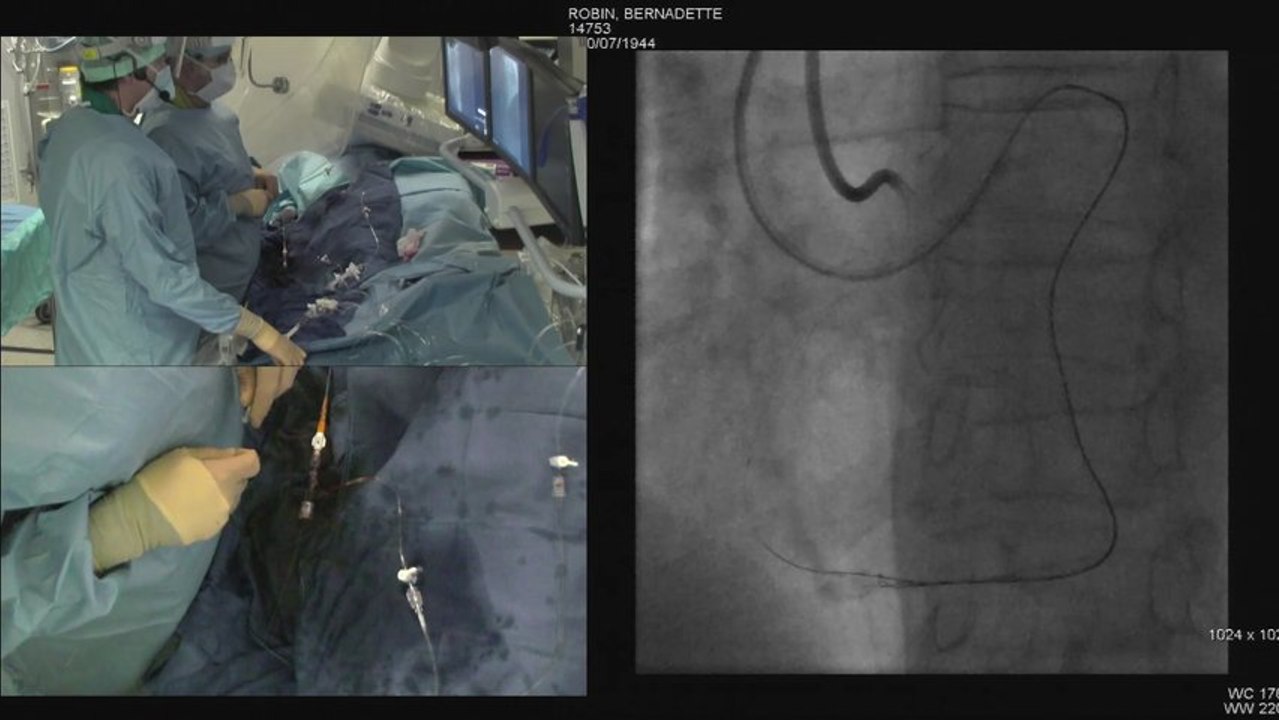

Endovascular Electronic Education : Discussions on recorded cases of CLI / BTK

Live from 35 th Charing Cross Symposium (London): ILEGx Collaboration Day